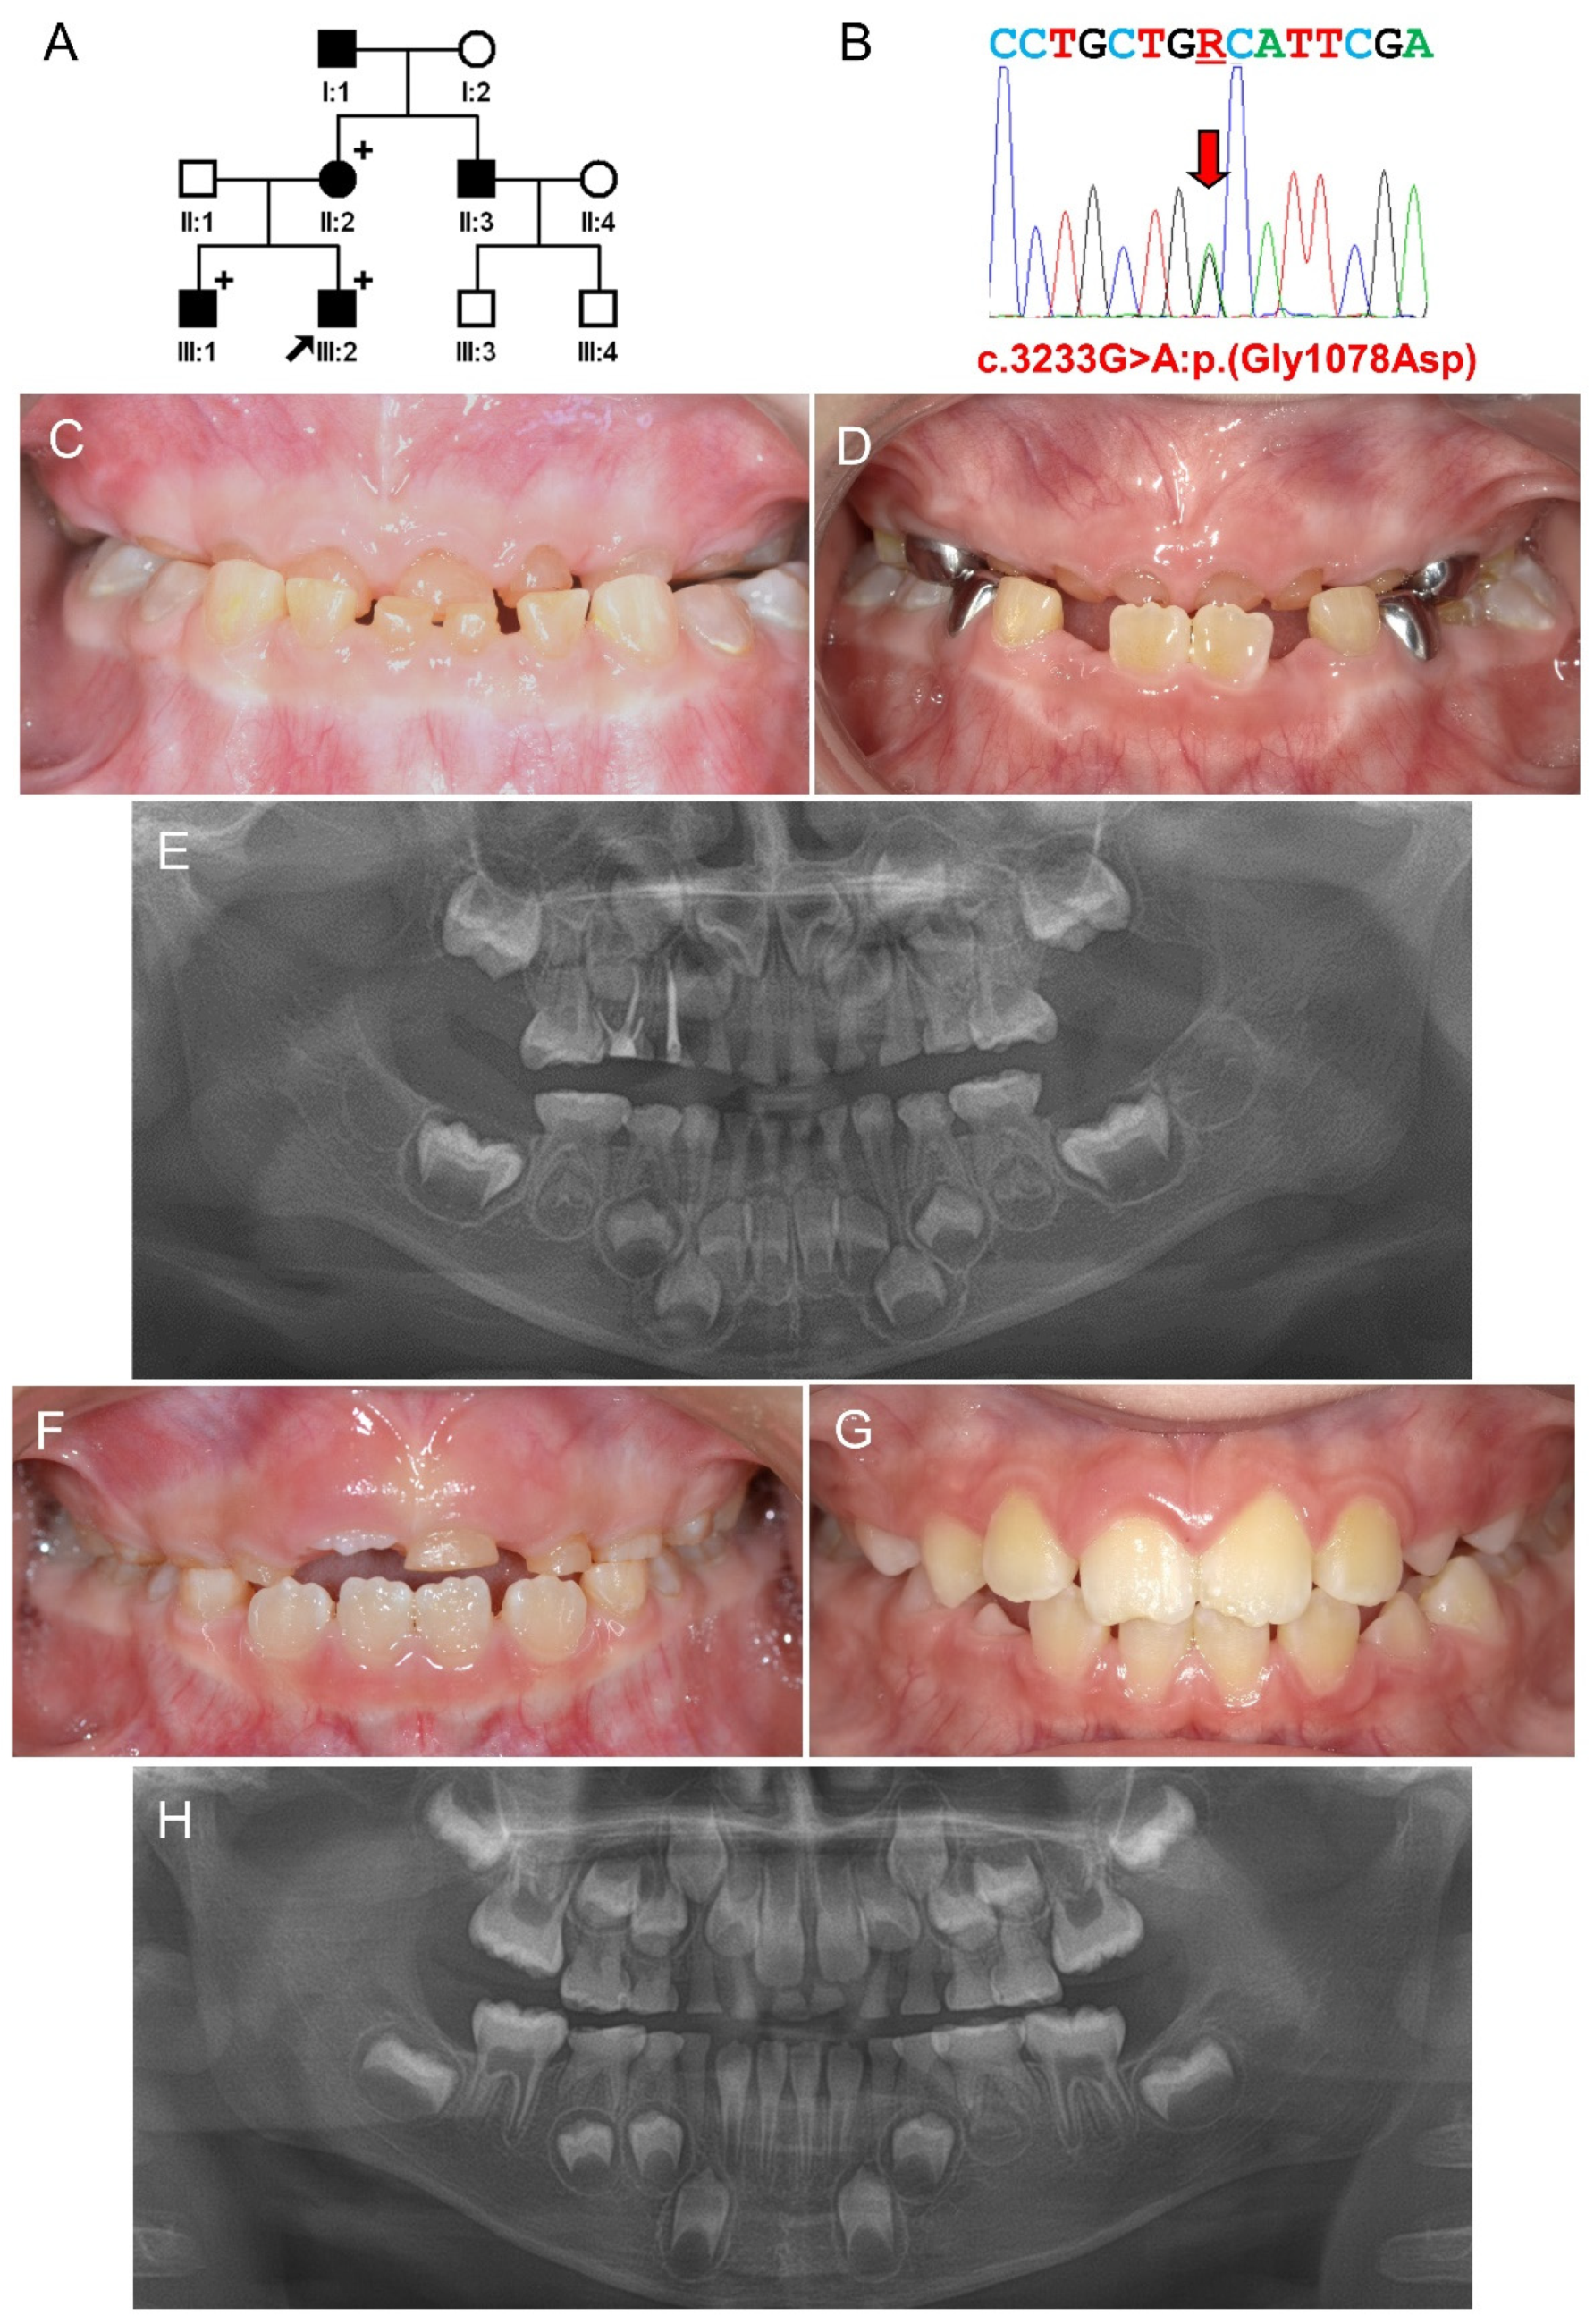

3.1. Family 1